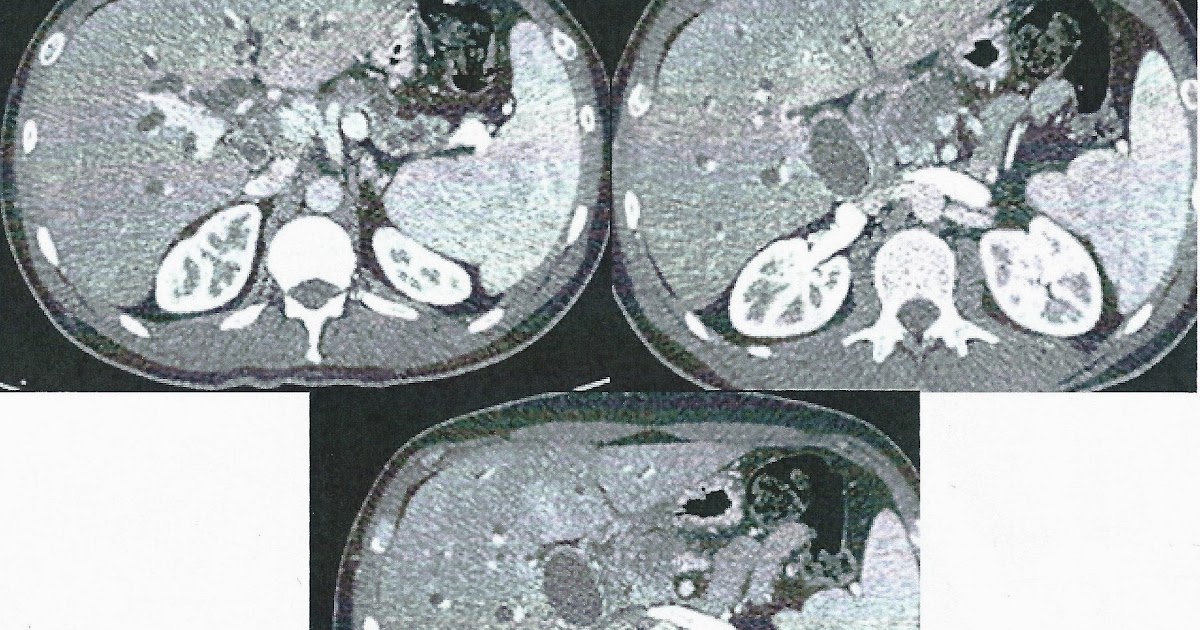

From drwaelelbanna.com

Intrahepatic Cholestasis Of Pregnancy (ICP) Dr. Wael Elbanna د Colestasis En Espanol Es cualquier afección en la que se reduce u obstruye el flujo de la bilis del hígado. la colestasis es una enfermedad compleja que se caracteriza por la reducción o interrupción del flujo biliar, que puede ser. la colestasis es una afección que afecta el flujo de bilis desde el hígado, lo que provoca problemas digestivos. La bilis. Colestasis En Espanol.